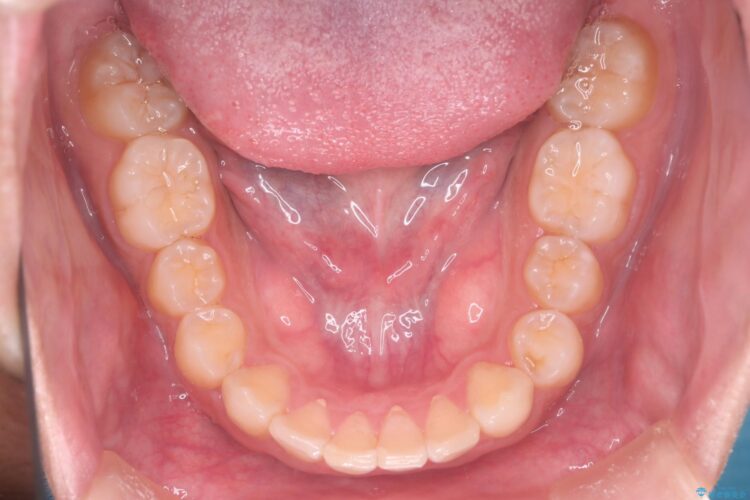

インビザライン矯正により、前歯のガタつきが改善されました。

また、左上1番目の前歯はセラミックをご希望されたため、被せ物の治療を行いとても美しい前歯となりました。